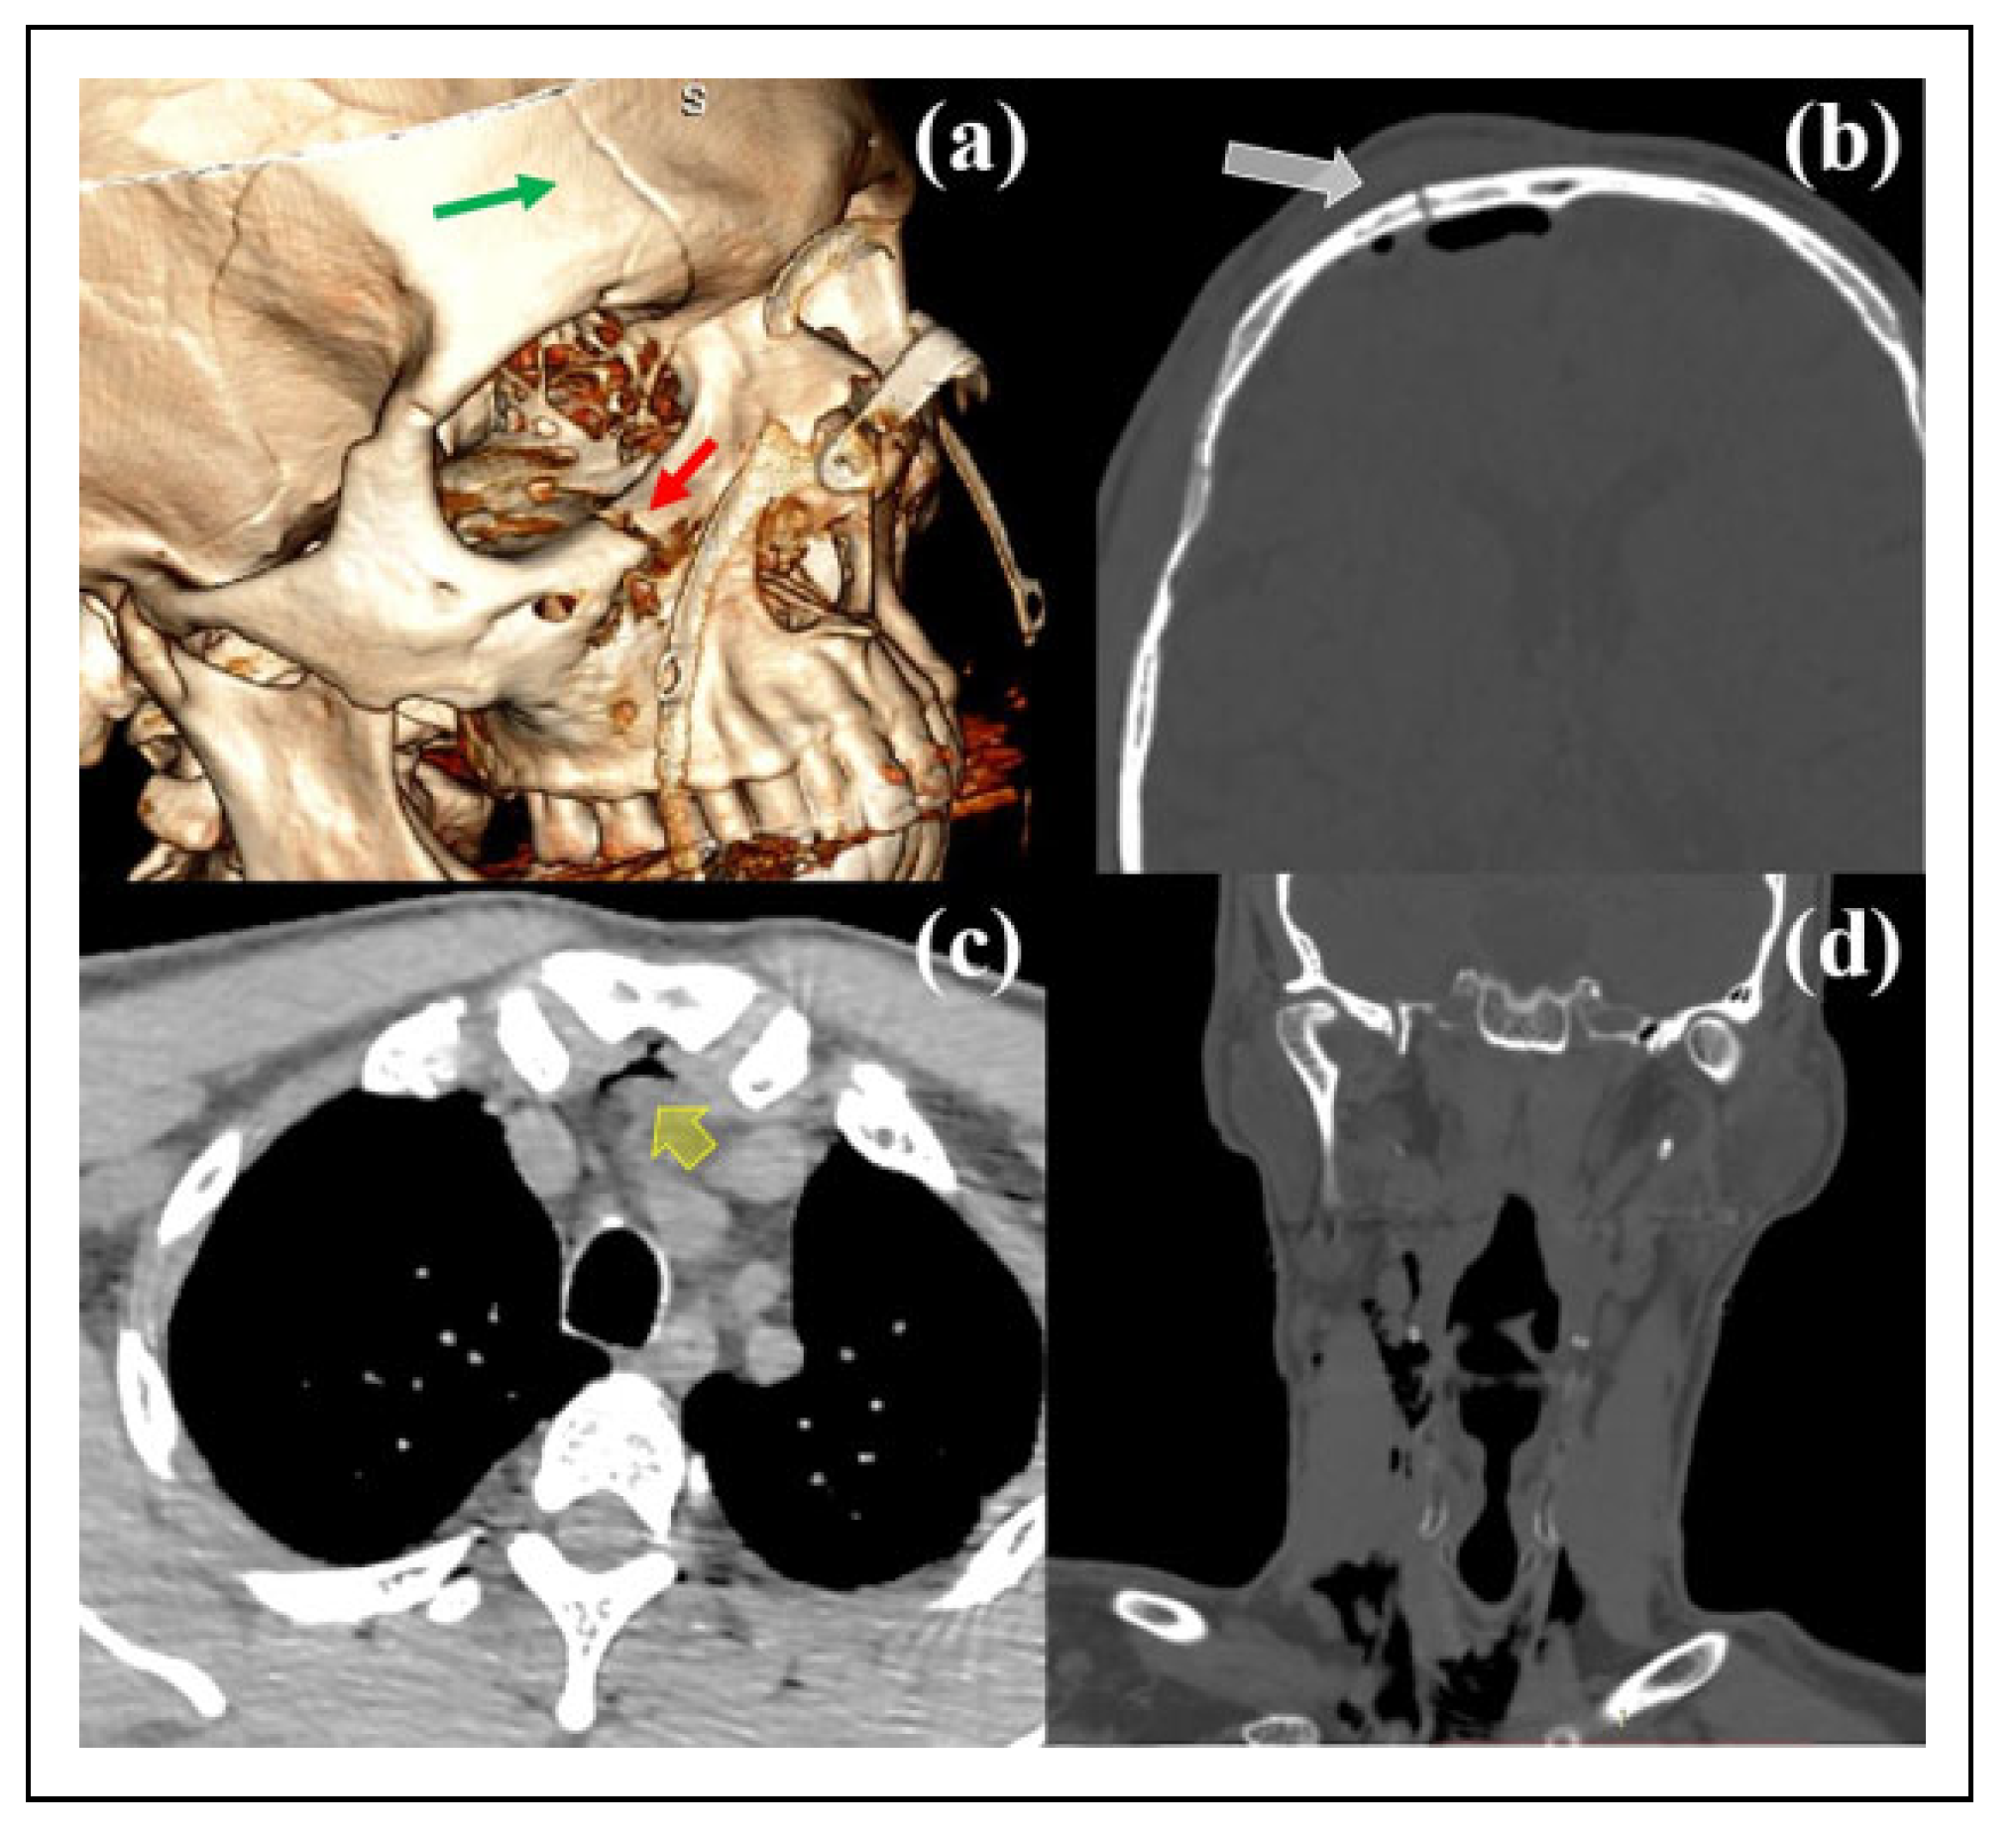

![]() |